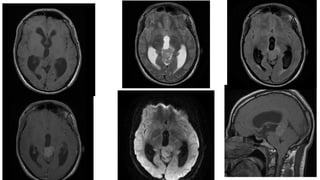

PINEAL CYST • Theyare common, usually asymptomatic, and typically found incidentally. • Common in women. • The cyst typically contains proteinaceous fluid that, as a result, does not follow CSF on imaging. • Internal haemorrhage may also be present

• 39.

CT Findings • Pinealcysts appear as well circumscribed fluid density lesions. • A thin rim calcification is seen in ~25%. • Thin, smooth peripheral enhancement is also often seen. • The internal cerebral veins are elevated and splayed by the cyst.

• 40.

T1 • Iso tohypointense compared to brain parenchyma • 55-60% are somewhat hyperintense when compared to CSF • Usually homogeneous in signal T2 • High signal • Usually slightly hypointense to CSF • Thin septations or small internal cysts may be present • FLAIR: high signal does not often suppress fully • DWI/ADC: they demonstrate no restricted diffusion

• 41.

• T1 C+(Gd) • ~ 60% of lesions enhance • Enhancement is usually thin (<2 mm), smooth and confined to the rim (either complete or incomplete) • It is important to note that if postcontrast imaging is delayed (60-90 min), gadolinium may diffuse into the cyst fluid and may lead to the mass appearing solid • In atypical cases enhancement may be nodular, or there may be evidence of previous hemorrhage into the cysts

Image courtesy ofRadiopedia rID: 2321

Image courtesy ofradiopedia rID: 2646

• #42 CT of the brain demonstrates no focal mass or abnormality. Incidental note is made of a 20 mm pineal cyst.

• #43 Incidentally well-circumscribed fluid density lesion with rim calcification is seen at pineal topography with no contrast enhancement.

• #44 MRI demonstrates a cyst in the pineal region. On T2 sequences, signal largely follows CSF but does not fully attenuate on FLAIR. Intrinsic pineal tissue masses tend to cause upward displacement of the internal cerebral veins. This is in distinction to tentorial meningiomas, which depress the cerebral veins. Internal cerebral veins (arrow) are elevated and splayed. Typical appearances of an incidental pineal cyst, almost certainly not the cause of the patient's headaches.